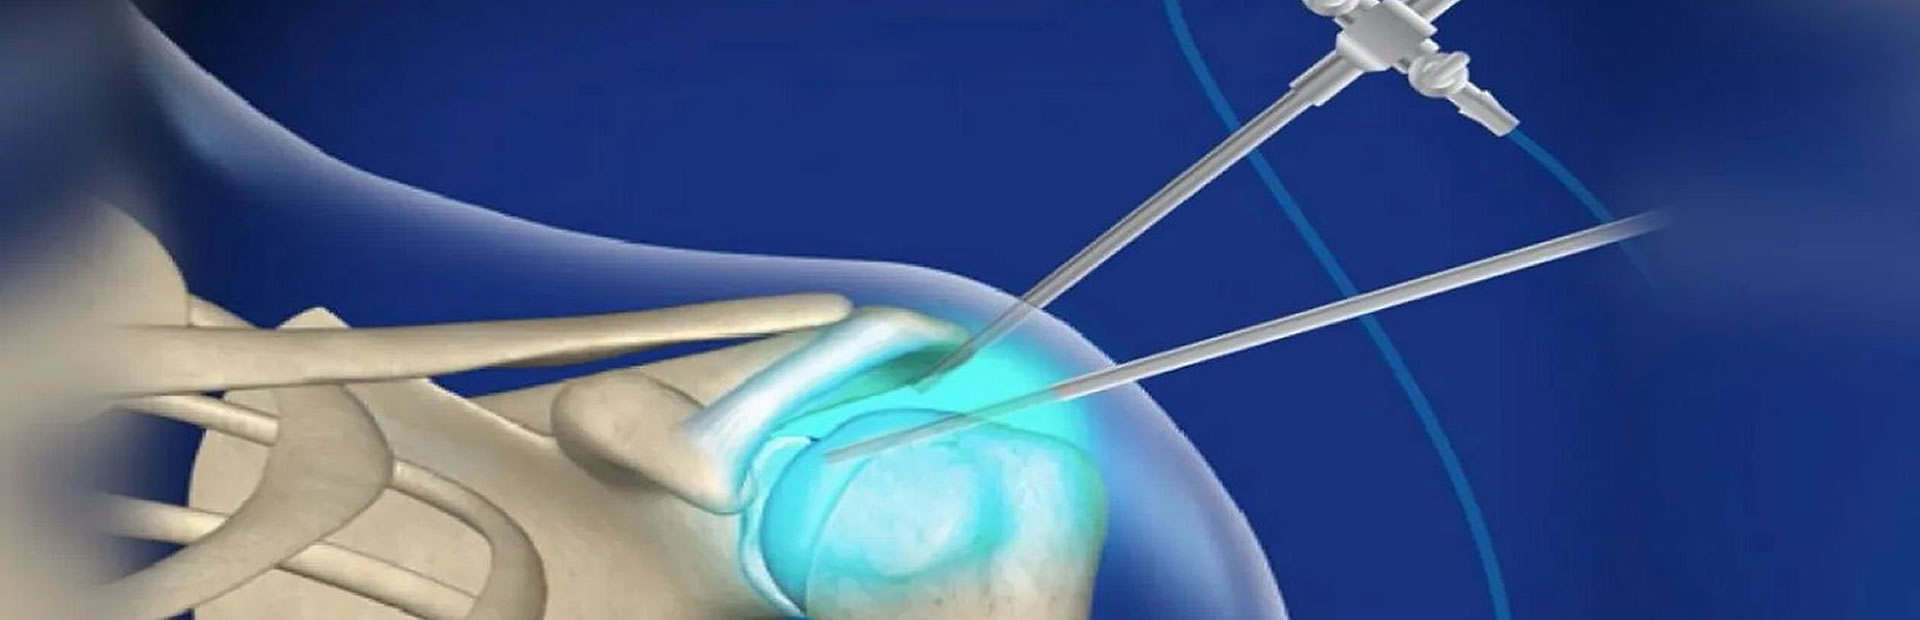

ARTROSCOPIA